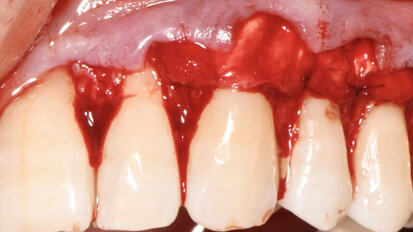

Arcate superiore e inferiore riabilitate con Chirurgia Guidata Simultanea full arch

Paziente donna di ottant’anni, presenta uno stato di salute ottimale, non assume farmaci. Dal punto di vista odontoiatrico chiede una riabilitazione delle...